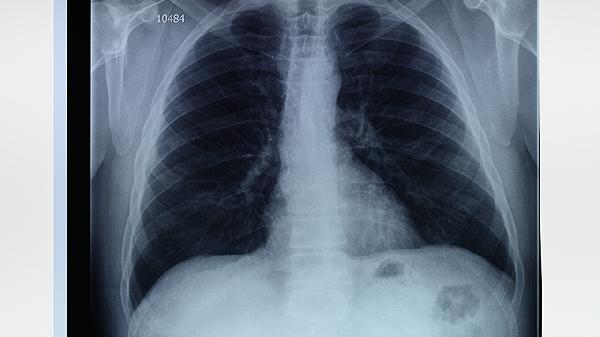

胸腔镜下肺大泡切除术适合反复气胸发作、肺大泡直径超过3厘米或伴有呼吸困难等症状的患者。肺大泡可能由慢性阻塞性肺疾病、肺气肿、先天性肺组织发育异常等因素引起,通常表现为突发胸痛、咳嗽、活动后气促等症状。

反复气胸发作的患者通过胸腔镜手术可降低复发概率。气胸发作时气体进入胸腔压迫肺部,导致肺组织塌陷。胸腔镜手术能直接切除肺大泡并缝合漏气部位,术后恢复较快。慢性阻塞性肺疾病合并肺大泡的患者在肺功能严重受损前手术效果更佳。这类患者肺组织弹性下降,大泡持续扩大会进一步挤压正常肺组织。手术需在稳定期进行,术前需评估肺功能。

直径超过3厘米的肺大泡即使无症状也建议切除。大泡体积增大会占据胸腔空间,影响正常呼吸功能。胸腔镜手术通过3-4个小切口即可完成操作,创伤小于开胸手术。伴有持续呼吸困难的患者需考虑手术干预。当大泡占据胸腔三分之一以上容积时,可能出现低氧血症。术后需配合呼吸康复训练改善肺功能。